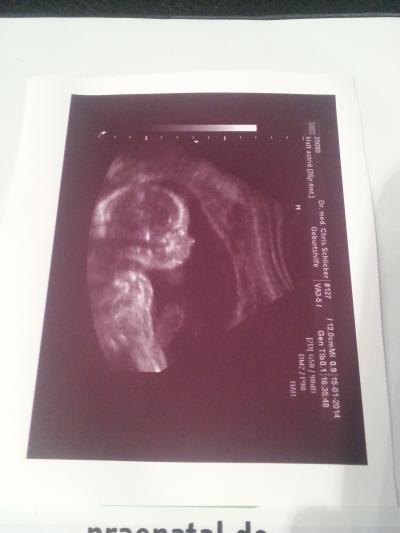

Wir musste uns lange gedulden, doch heute hat sie sich offenbart... es wird ein Mädchen Sie ist jetzt ca. 23 cm groß und hat eine Vorliebe dafür die Händchen vor's Gesicht zu halten und am Daumen zu lutschen

Bild zu Ultraschall und Outing bei 20+6 - Forum für Mai - Mamis